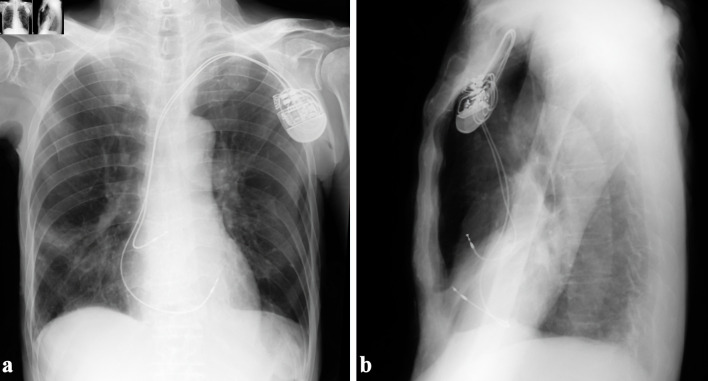

An 83-year-old man underwent dual-chamber pacemaker placement for complete atrioventricular block at another hospital. The active-fixation ventricular lead was positioned on the free wall of the anterior right ventricle. Ventricular pacing failure occurred on the day after pacemaker implantation, and fluoroscopy revealed right ventricular (RV) lead perforation. The patient was transferred to our hospital, and chest computed tomography revealed a severe pneumothorax and moderate pneumopericardium. These symptoms were relieved after chest tube drainage, and the patient's hemodynamics stabilized. The RV lead was percutaneously removed using simple traction under fluoroscopic guidance with cardiac surgical backup and was uneventfully refixed to the RV septum. Although there have been several reports of pneumopericardium caused by atrial lead perforation, there are very few cases related to RV lead. Pneumopericardium complicated by pneumothorax due to RV lead perforation can be relieved using chest tube drainage without the need for pericardiocentesis.